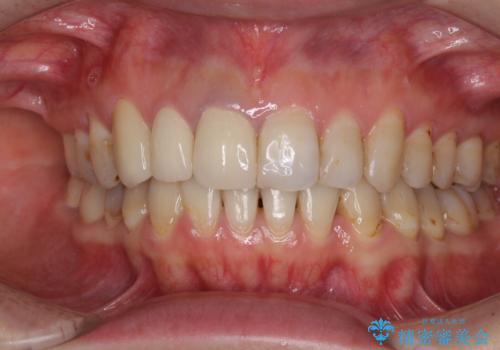

- 前歯の歯並びやむし歯治療の跡、奥歯の銀歯を気にして来院された患者様です。

インビザラインによる矯正治療の後に虫歯や銀歯をセラミックにて補綴することとしました。

前歯のむし歯治療の跡や奥歯の目立つ銀歯がなくなり、明るい口元になりました。